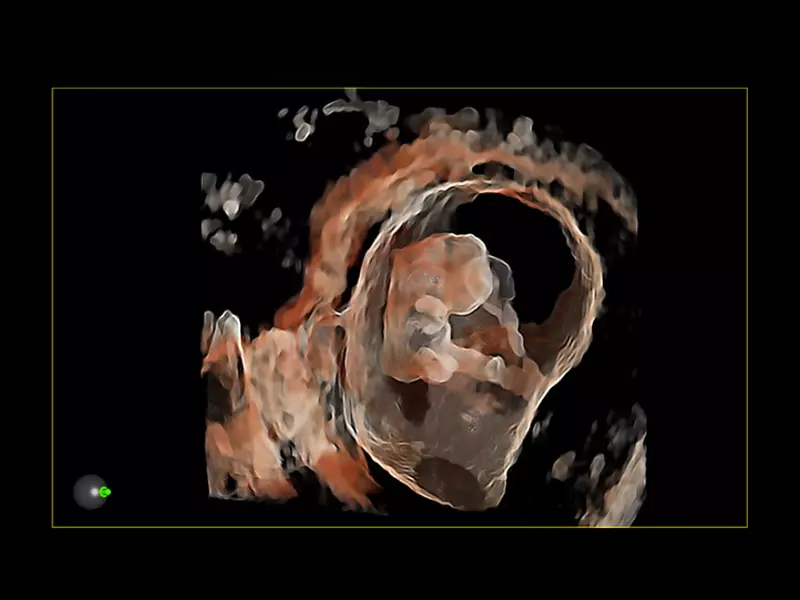

MyLab™9 Platform - Baby Face rendering in real-time with XLight

MyLab™9 Platform - Baby Face rendering in real-time with XLight